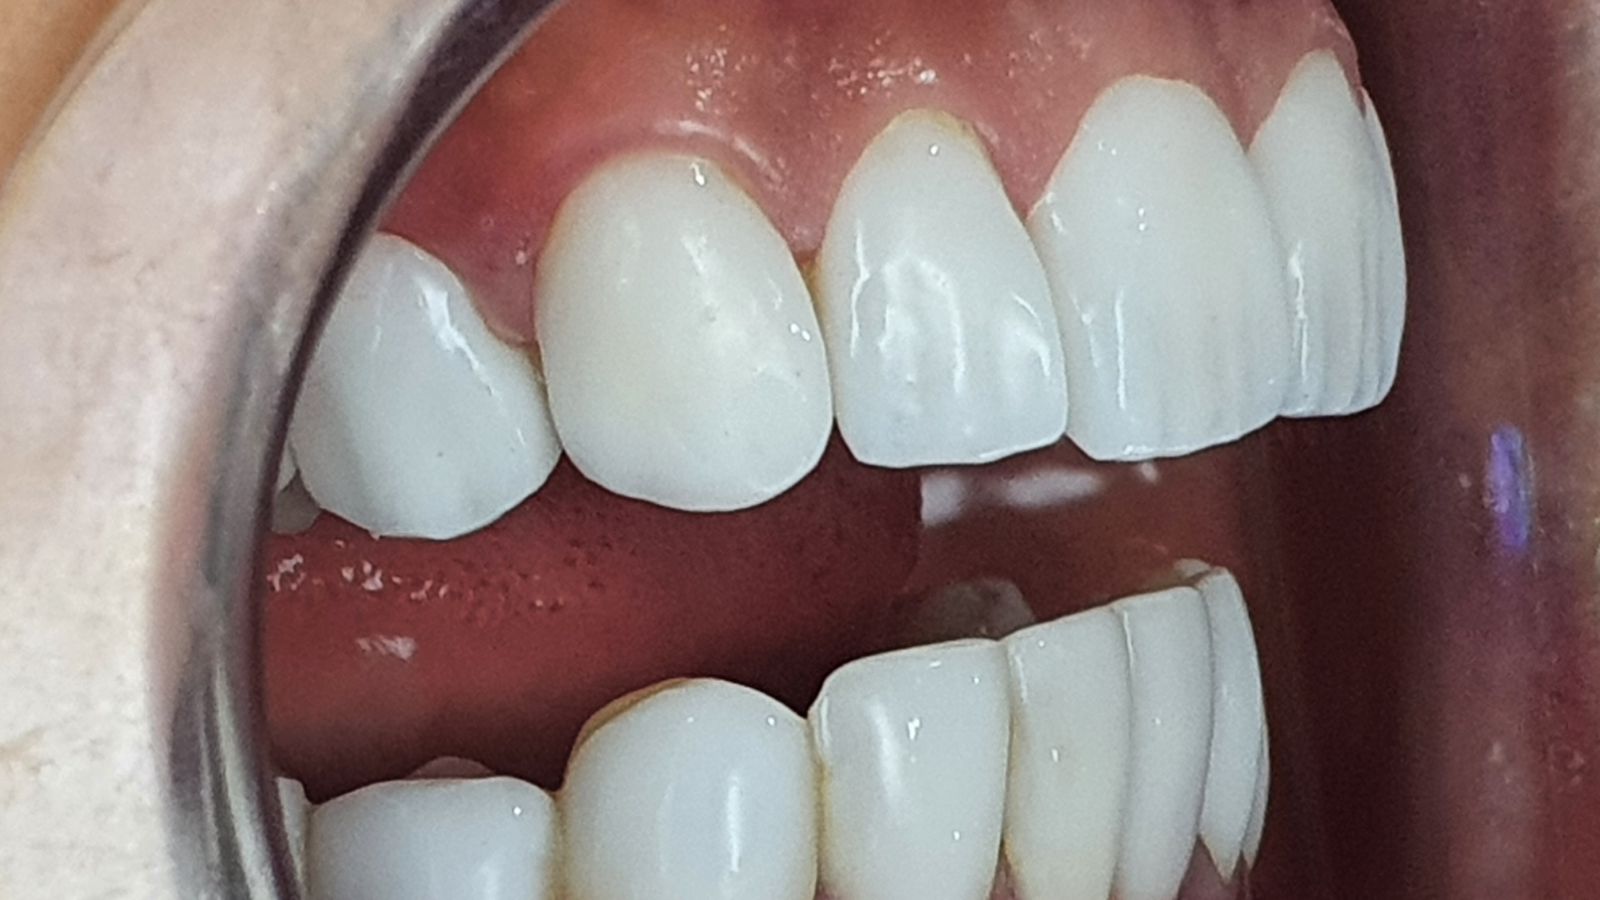

Réhabilitation esthétique après orthodontie : full-zircone & disilicate de lithium

Une jeune patiente arrive en fin de traitement orthodontique pour un déficit esthétique.

La difficulté réside dans la réalisation de prothèses différentes dans le même secteur : jongler avec la full-zircone et le disilicate de lithium.

Ce challenge fut le sujet de mon mémoire du DU d’esthétique de Strasbourg en 2008.

L’expérience et l’investissement dans le digital depuis 2017 rendent le résultat plus prévisible.

Images :